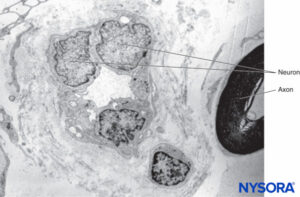

EPINEURIUM

The outermost sheath of the epineurium consists of moderately dense connective tissue that binds nerve fascicles (Figures 3, 19, and 20). Epineurium merges with adipose tissue surrounding peripheral nerves, particularly in subcutaneous tissue. The amount of epineurial tissue varies along a nerve and is more abundant around joints. The thickness of the epineurium varies in different nerves and in different locations of the same nerve. For instance, the average thickness of the epineurium is 22% of the ulnar nerve at the level of the elbow and 88% of the sciatic nerve at the gluteal level.

In general, the epineurium represents between 30% and 75% of the cross-sectional area of a nerve. The proportion of epineurium is higher in larger nerves with increasing numbers of nerve fascicles. However, the epineurium is absent around monofascicular nerves and at nerve endings.The epineurium contains adipocytes, fibroblasts, connective tissue fibers, mast cells, small blood and lymph vessels, and small nerve fibers innervating the vessels. Epineurium is a permeable structure, and its fibroblasts are ultrastructurally identical to fibroblasts elsewhere in the body. Scattered throughout the epineurium, fibroblasts form the epineurial collagen, the most prominent component of this layer. As collagen is a protein stained by most acid dyes, collagen fibers turn weak pink wiht eosin in preparations stained with hematoxylin-eosin. Under the electron microscope, fibers of mature collagen have frecuent cross bandings. Elastic fibers are also present, and these are considerably more compact than collagen fibers. They stain weak pink in sections stained with hematoxylin and eosin, brown with orcein, and blue-purple with resorcin-fuchsin. In electron micrographs, elastin fibers typically appear more stained (darker) at the periphery and are embedded in a sub-stance containing thinner elastin filaments.The epineurium of some nerves contains a considerable amount of fat, as is the case with the sciatic nerve. The common peroneal and tibial nerves, however, contain less fat than the sciatic nerve, and usually the former contains less fat than the latter.

Seen under the microscope, intraneural adipose cells resemble honeycombs, with empty vacuoles due to fat dissolution, during the fixation process (Figure 21). Mast cells are distributed throughout connective tissue and are often located in the proximity of small blood vessels. Vasa nervorum supplying peripheral nerves arise from branches of regional arteries. Branches from these arteries enter the epineurium to form an vascular plexus (Figures 22 and 23). From the plexus, vessels penetrate the perineurium and enter the endoneurium as arterioles and capillaries. In nerves consisting of several fascicles, arteries, veins, and lymphatics run longitudinally and parallel to nerve fascicles.